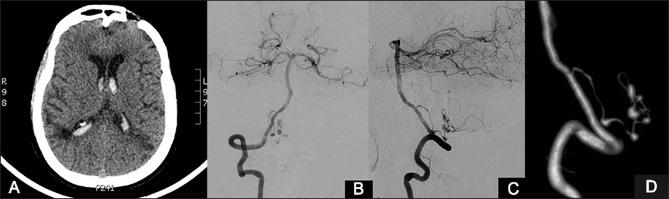

Primary angiitis of the central nervous system (PACNS) is a rare disorder affecting both medium- and small-sized vessels. Intracranial haemorrhages though less reported are in the form of parenchymal haemorrhage and subarachnoid haemorrhage. We report a case of PACNS with intraventricular haemorrhage due to aneurysms secondary to progression of vasculitis.

中枢神经系统原发性血管炎(PACNS)是一种罕见的疾病,可累及中小血管。颅内出血虽报道较少,但形式为脑实质出血和蛛网膜下腔出血。我们报告一例因血管炎进展继发动脉瘤导致脑室出血的PACNS病例。